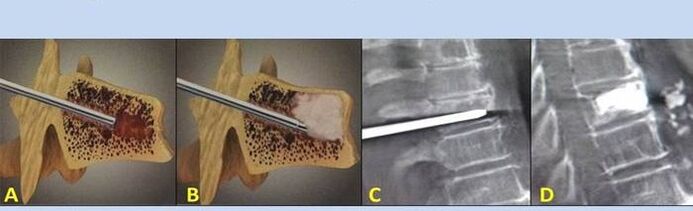

- Nucleoplastia – extirpación do núcleo do disco intervertebral. A operación alivia a presión sobre as terminacións nerviosas.

- Vertebroplastia de punción – Método de estabilización das vértebras. Durante o procedemento, o médico enche as cavidades da columna con cemento óseo.